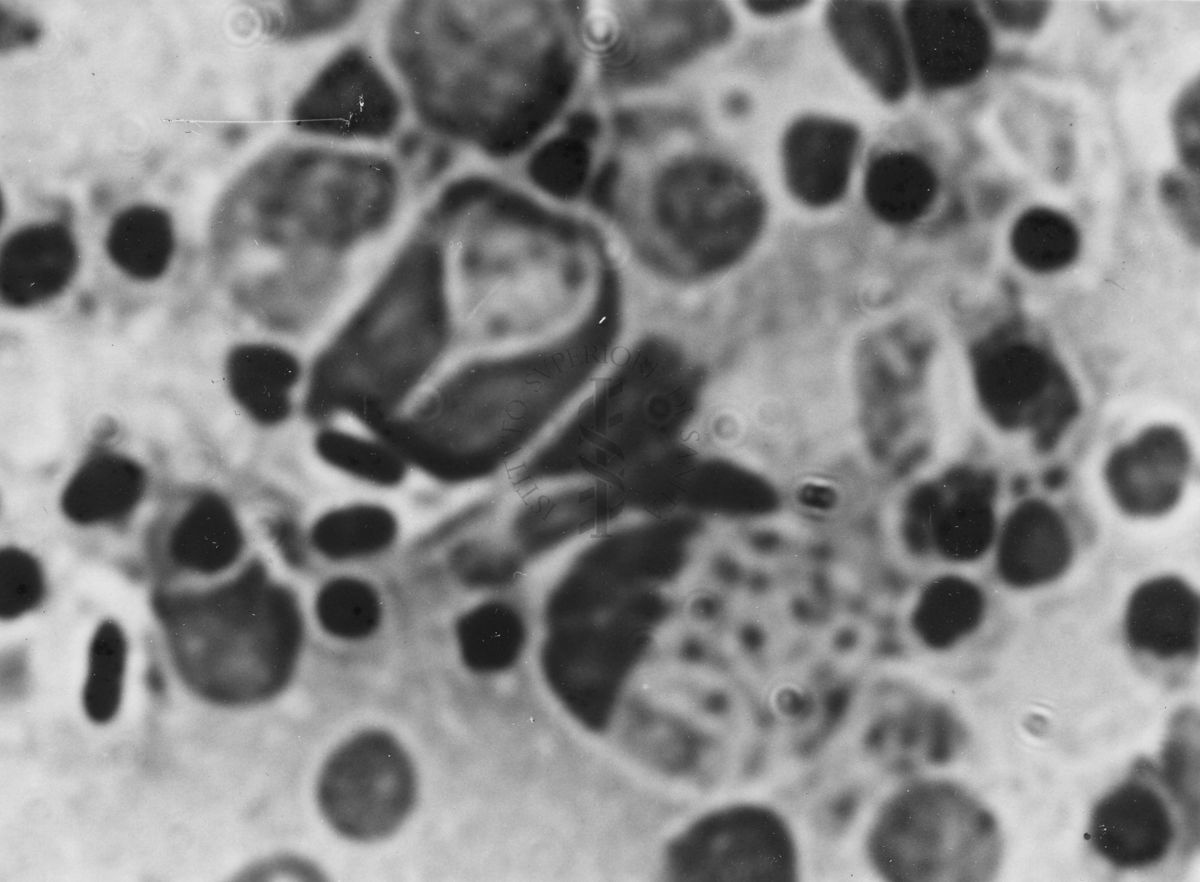

Immagini di Emoprotozoi